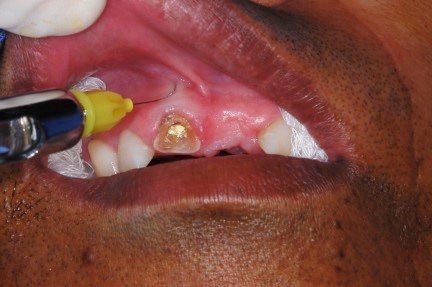

Paciente do sexo masculino, 51 anos, casado, negro, procurou a Universidade Tuiuti do Paraná, em 19 de fevereiro de 2013, para obturação do dente 11, queixando-se de um buraco na gengiva, em cima do elemento, por onde drenava grande quantidade de secreção purulenta.

Ao exame radiográfico, observou-se extensa área radiolúcidas, constatando uma fístula, lesão periapical envolvendo região periapical do referido dente.

- Figura 2 – Radiografia periapical do ápice com a presença de fístula.